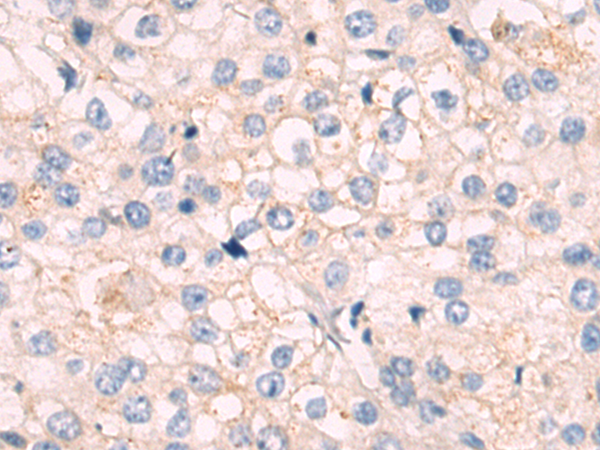

分类: 科研抗体货号: P12502别名:应用: WB,IHC反应种属: Human